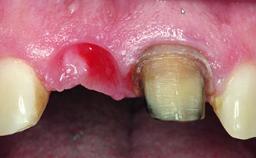

Replacement of an Upper Right Central Incisor with a Root Fracture, Early Placement of an RC Bone Level Implant, Variobase Abutment

A healthy 28-year-old female patient presented for a consultation on treatment options to restore her upper right central incisor. At the clinical examination, the tooth responded to percussion and palpation. The gingiva was red and slightly swollen, with a mid-facial probing depth of 10 mm. The upper right lateral incisor showed no signs or symptoms, did not respond to exploration and percussion, and the vitality test was positive. The periapical radiograph revealed that tooth 11 had been endodontically treated, with no lesion evident at the apex. A small radiopaque calcified structure surrounded by a narrow radiolucent zone (3 × 3 mm) was present at the apex of tooth 12.

Soft Tissue Contour and Volume Slightly compromised